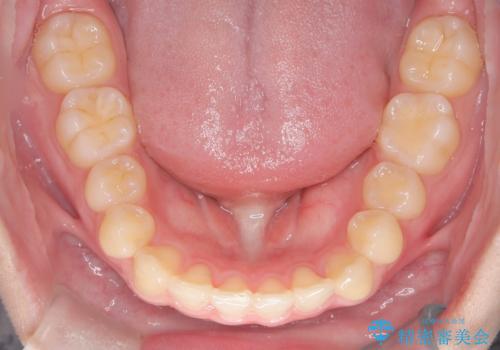

マウスピース矯正で前歯のガタツキを改善! 短期間で治療完了

前歯のガタツキを改善する治療法として、マウスピース矯正が適していることが多いです。

マウスピース矯正は、金属製のブラケットやワイヤーを使用せずに、透明なマウスピースを装着して歯を移動させる方法です。そのため、目立たず、痛みも少ないです。